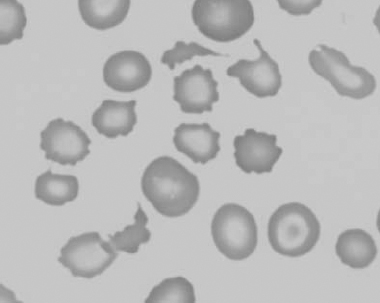

Figure 1.7 Canine blood film showing blister cells due to oxidative damage (also see color section).

Figure 1.8 Canine blood film showing codocytes. Up to 50% codocytes may be normal in a dog (also see color section).

Figure 1.9 Canine blood film showing eccentrocytes due to oxidative damage (also see color section).

Figure 1.10 Canine blood film showing echinocytes I (also see color section).

Figure 1.11 Canine blood film showing echinocytes III (also see color section).

Figure 1.12 Feline blood film showing echinoelliptocytes (also see color section).

Figure 1.13 Canine blood film showing Heinz bodies and ghost cells due to oxidative damage. There are also several polychromatophils (also see color section).

Figure 1.14 Canine blood film stained with new methylene blue, to demonstrate Heinz bodies (also see color section).

Figure 1.15 Canine blood film showing keratocytes and schizocytes (erythrocyte fragments) due to fibrin strand injury. A codocyte and a polychromatophil also appear in the field (also see color section).

Figure 1.16 Feline blood film showing Mycoplasma hemofelis organisms (hemobartonellosis). Organisms are not always visible in blood smears from infected cats (also see color section).

Figure 1.17 Canine blood film showing several macrocytes (also see color section).

Figure 1.18 Canine blood film showing a metarubricyte There is also a polychromatophilic macrocyte in the field (also see color section).

Figure 1.19 Canine blood film showing microcytic, hypochromic erythrocytes consistent with iron deficiency anemia. There are two polychromatophils in the field, indicating that the anemia is regenerative (also see color section).

Figure 1.20 Canine blood film showing two macrocytes with nuclear remnants (also see color section).

Figure 1.21 Bovine (calf) blood film showing marked poikilocytosis (normal?) (also see color section).